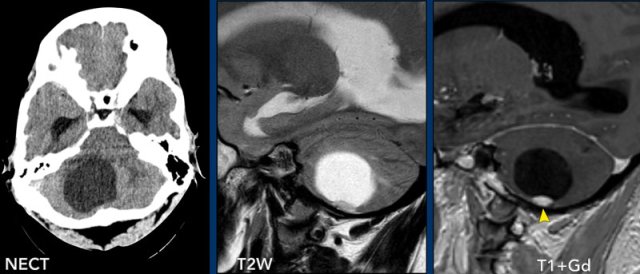

These images are of a 9-year old child who presented with headache.

Images

there is a large cystic posterior fossa mass with compression and

obstruction of the fourth ventricle and brainstem.

A solid contrast enhancing

nodule is present, as well as enhancement of the cyst wall.

Conclusion

Most likely diagnosis at this age is a pilocytic astrocytoma

These images are of a 3-year old child who also presented with headache.

There are two important findings.

Take a closer look at the images and then continue reading.

Large cyst with enhancing nodule in the posterior fossa..

Notice that the wall of the cyst enhances.

The nodule is not located on the pial side (inner part of the meninges) unlike in a hemangioblastoma.

Most likely diagnosis at this age is a pilocytic astrocytoma.

The enhancing wall is part of the tumor and needs to be resected.